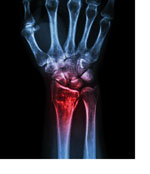

A wrist fracture, particularly a distal radius fracture, is a common injury that can significantly impact daily life. Whether from a fall, sports injury, or accident, recovering properly is essential to restore mobility, strength, and function. While time plays a crucial role in healing, occupational therapy can accelerate recovery, ensuring the wrist regains full strength and flexibility. In this guide, we will explore the healing process and benefits of occupational therapy.

Healing from a broken wrist follows a structured process involving three major phases. The first stage, known as the inflammation phase, lasts from 0-7 days. During this time, the body works to form a blood clot around the fractured bone, and soft tissues begin repairing the injury. Patients typically experience swelling and pain as the body initiates its natural healing process.

For patients requiring surgical treatment, procedures such as internal fixation with screws or plates, percutaneous fixation or external fixation may be used to stabilize unstable fractures. Following surgery, occupational therapy helps manage pain, swelling, and stiffness, and promotes ROM and strength to regain functional use of your wrist and hand.